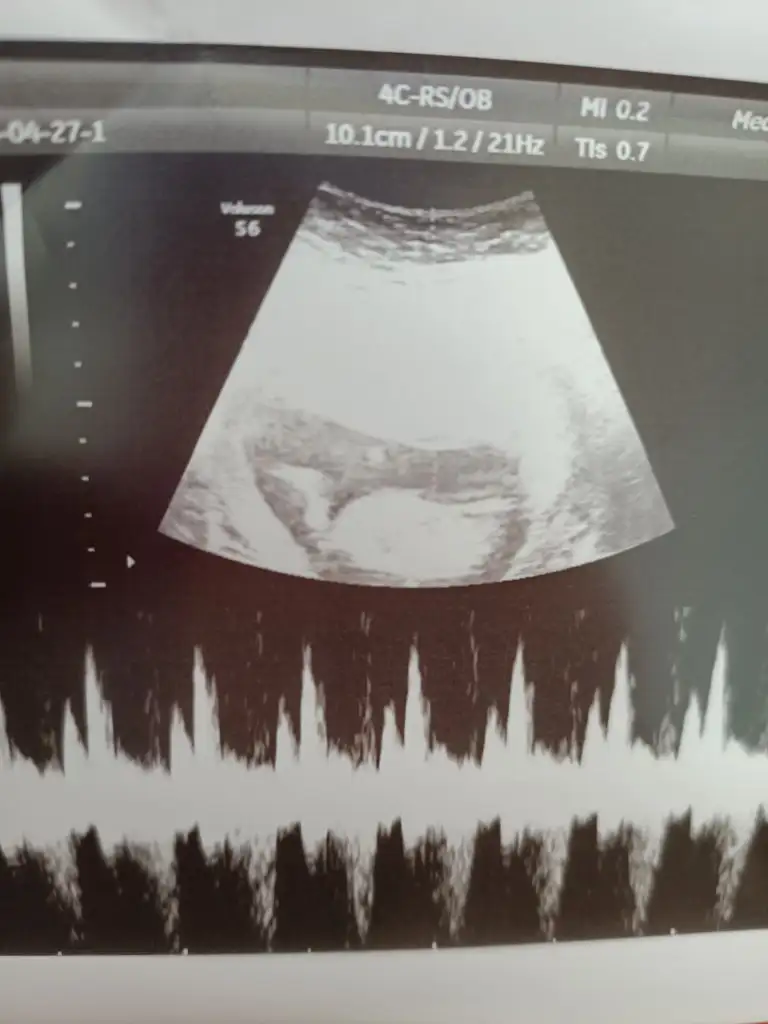

Canim yeni fotolarim geldi bakabilir misin bir Dr erkek dedi Kordon'da olabilir dedi..bugünde başka Dr gittim kıza benziyor dedi..kalp atışı olan fotoda solda bacakları nubu var yandan da baktı dr görebilmek için .sen ne düşünüyorsun

Emin olmadım ama kız sanki önceki usgde kız demiştim